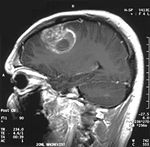

一名15岁男孩儿的联合国健康组织四级胶质母细胞瘤核磁共振成像

使用核磁共振成像胶质母细胞瘤往往呈环状,但是这个形状并不一定就是胶质母细胞瘤了,因为脓疮、远端转移等现象也可能是这个形状[21]。假如核磁共振成像或X射线计算机断层成像怀疑胶质母细胞瘤的话需要通过立体定位活组织检查或开颅手术来获得癌组织进行化验确诊。由于癌症的级别是根据癌最恶化的部位来确定的,检查时可能只获取一个小部分的组织,因而导致把癌的级别划轻。通过灌注核磁共振成像可以确定癌内的血流,使用活体磁共振波谱分析可以测量癌的新陈代谢率,这些手段都可以为核磁共振成像提供帮助,但是最终还是需要组织分析来确诊。